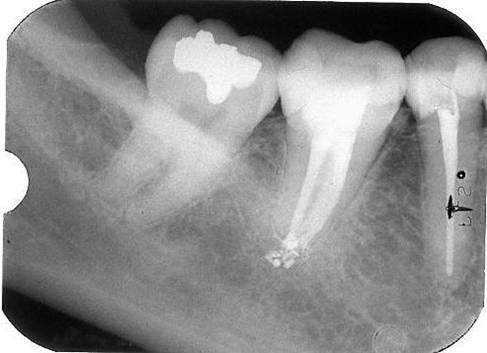

Een “C-shaped canal”

Een C-shaped canal komt af en toe voor bij de ondermolaren. Meer in de tweede ondermolaar dan in de eerste.

Herkenning is belangrijk omdat anders zoals altijd naar de 3 of 4 kanalen wordt gezocht die zich normaal in een ondermolaar bevinden. Uiteindelijk is dan een groot deel van het kanalensysteem niet gereinigd. Met een behandelmicroscoop valt onmiddellijk te zien dat het niet om normale kanalen gaat maar om een complex halve maanachtig systeem.

Goed preparen van een C-shaped canal is buitengewoon lastig. Het is handig om distolinguaal en mesiolinguaal eerst 2 kanalen te preparen. Dit kan op de gebruikelijke wijze zoals beschreven bij de primaire endodontische behandeling. Vervolgens kan op twee manieren verder worden gegaan. Op elke plaats waar een handvijl nog naar apicaal wil wordt opnieuw een kanaal geprepareerd. Uiteindelijk is het grootste deel van het complexe kanaalsysteem dan wel schoon geprepareerd. Een andere mogelijkheid is om vanuit de reeds geprepareerde 2 kanalen met ultrasone vijlen het gehele halve maan gebied te reinigen. Dit kan ook met behulp van Rotary shaping files. Ook Gates Glidden drills zijn erg handig om “de halve maan” te reinigen.

Vullen van het complexe kanalensysteem is het gemakkelijkst te doen met een combinatie van System B en Obtura II . De laterale condensatie techniek is hier minder geschikt.

Met System B worden de apicale delen van de kanalen gevuld en vervolgens wordt met de warme guttapercha spuittechniek van Obtura II de rest van het complexe systeem opgevuld.